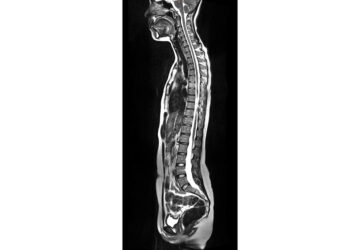

This photo provided by Prenuvo in July 2024 shows an MRI scanner. Magnetic resonance imaging uses magnetic fields to produce detailed images of organs, bones and other structures inside the body. Unlike many other types of scans, MRIs don't use radiation. (Prenuvo via AP)

MRI stands for magnetic resonance imaging. It’s a type of medical scan that uses magnetic fields to produce detailed images of organs, bones and other structures inside the body. Unlike many other types of scans, MRIs don’t use radiation.

Doctors will order an MRI to help diagnose cancer, brain injuries, damaged blood vessels and other medical conditions. Full-body scans can take an hour or more, with patients lying motionless inside a cylindrical tube.